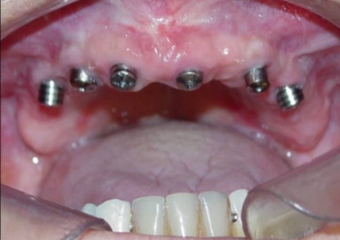

Imagem dos Implantes Superiores Instalados